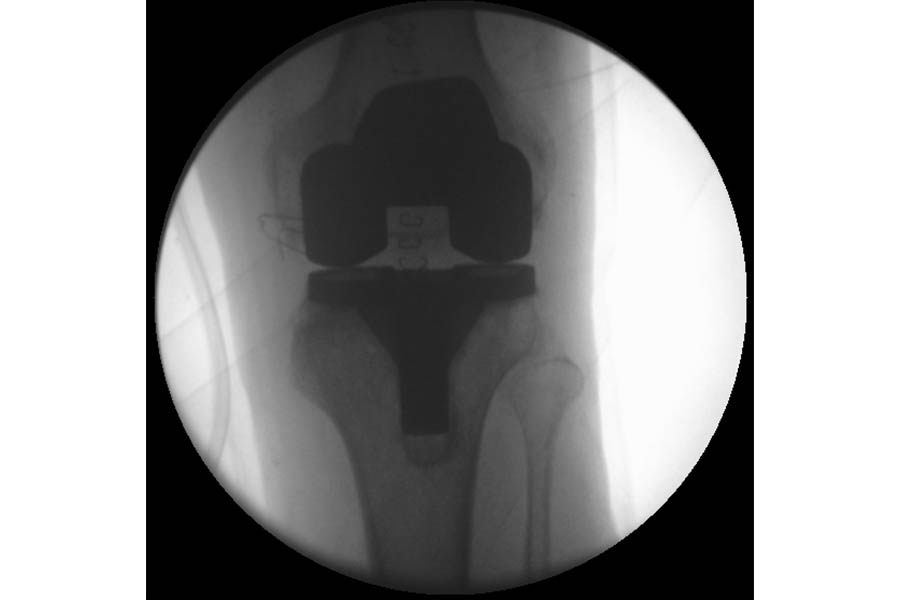

Total Knee Replacement

Case 3